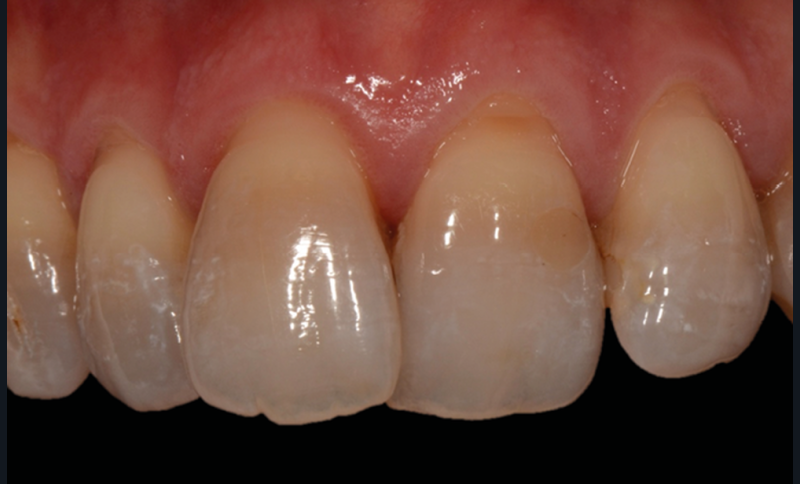

C’est à ces questions que nous permettront de répondre les deux premiers conférenciers, parodontologistes : le Dr Béatrice Straub nous présentera le renfort parodontal minéralisé, technique qu’elle a développée et pratique depuis de nombreuses années, pour éviter les préjudices des mouvements orthodontiques à risque, notamment lors des décompensations préchirurgicales (fig. 1a-d) ; le Pr Anton Sculean abordera le thème des greffes, avec leurs indications, les différentes techniques à privilégier et illustrera ses propos par de nombreux cas cliniques aux résultats esthétiques impressionnants.

Le Pr Olivier Sorel insistera sur l’importance du respect des formes et des proportions anatomiques, pour éviter de voir apparaître, notamment chez les adultes, de très inesthétiques triangles noirs lors de la phase d’alignement (fig. 6a-b). Il présentera sa démarche diagnostique (évaluation de la forme des dents et de la dysharmonie dento-dentaire, fig. 7a-c) et l’intégration de la réduction amélaire proximale au plan de traitement, afin de s’assurer, en fin de traitement, la présence de papilles gingivales et donc d’un sourire harmonieux (fig. 8a-d).

Les Drs Marie Clément et Clara Marcoux aborderont ensuite les différents apports de la dentisterie esthétique aux traitements orthodontiques. Les problèmes de dyschromies isolées ou généralisées, congénitales ou acquises seront développés ainsi que les anomalies de proportions dentaires (dents riziformes…), le maquillage (transformation d’une canine en incisive latérale…) et le remplacement des dents antérieures. Les auteurs présenteront l’intérêt du Digital Smile Design dans le diagnostic et la communication et l’arsenal thérapeutique à notre disposition pour améliorer la satisfaction de nos patients (éclaircissement, traitement des taches de l’émail, composites stratifiés, fig. 9a-d).